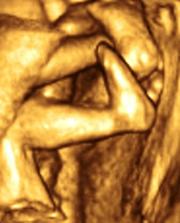

Ako nám to ide...